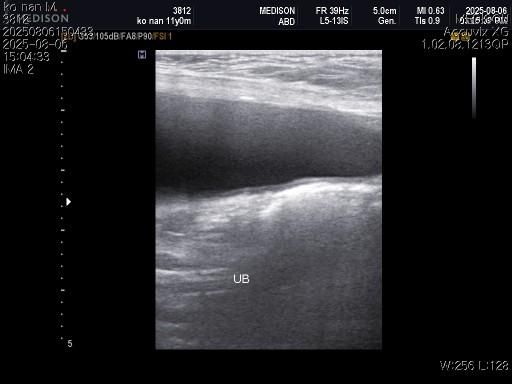

1) 혈액검사와 엑스레이 그리고 초음파상 혈뇨의 원인이 나타나지가 않는지 궁금합니다.

3) 신장결석이 어느정도인지도 궁금합니다.

4) 양쪽 부신의 크기가 궁금합니다.

5) 지방간이 있는지 있으면 어느정도인지 궁금합니다..